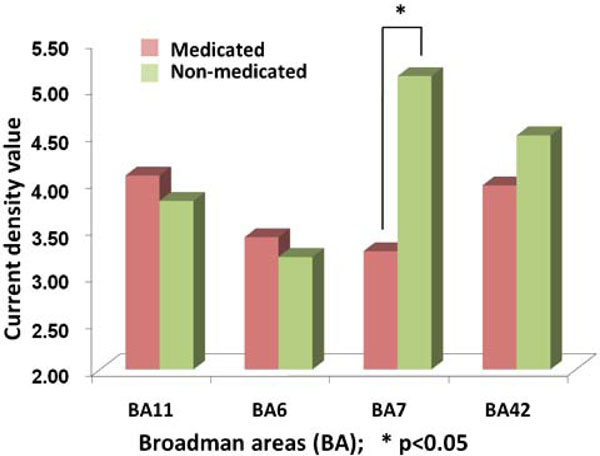

The comparison between the evoked responses in medicated and non-medicated conditions have been compared for the abovementioned four ROI. A paired t-test has shown a significant difference for BA7 location (p=0.011) Fig. (7). Accordingly, major reduction has been localized at an area with highest non-medicated activity.

The comparison of activity obtained from Current Density Values (CDV) of sLORETA procedures in BA11, BA6, BA7 and BA42. The vertical bars denote the average CDV where left side of the pairs shows the medicated groups. The asterix highlights the statistically significant difference (p<0.05).